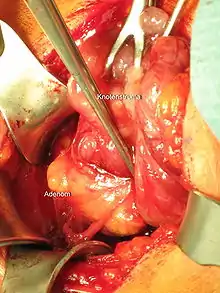

Паратиреоїдектомія — це хірургічна операція з видалення паращитоподібної залози. Показаннями до виконання цього оперативного втручання є злоякісні (рак) та доброякісні (аденома) пухлини паращитоподібної залози.[1]

- Коли щитоподібна залоза достатньо візуалізована, проводиться ревізія задньої поверхні для ідентифікації ураженої патологічним процесом паращитоподібної залози

- Ідентифікація паращитоподбіних залоз відбувається під час мобілізації долей, після чого в безпосередній близькості, але поза межами капсули патологічного вогнища, поетапно накладаються затискачі, тканина відсікається та накладаються лігатури.